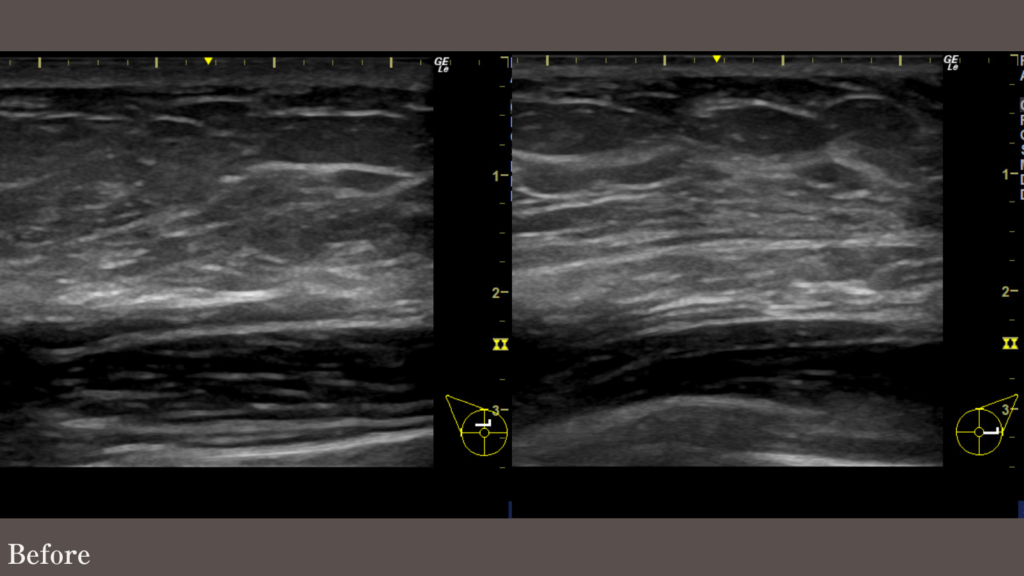

27歳男性 172cm 86.8kg BMI29.3

少し乳腺が濃いタイプでしたが、胸部 側胸部 脇肉前VASER脂肪吸引を行い、Tシャツが着られるようになりました。